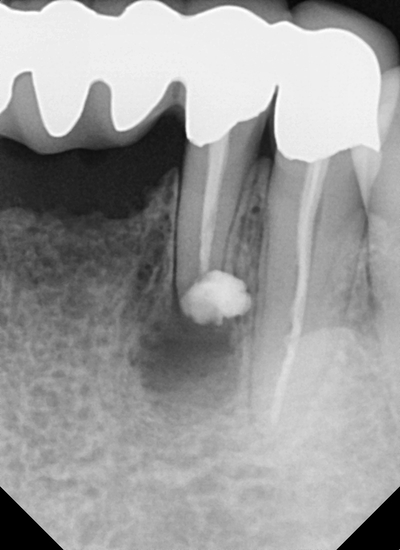

이제 <MTA> 라는 생체 친화적 재료로 세균감염이 되지 않게

치아 끝부분을 막아준 후 마무리합니다.

경우에 따라,

염증으로 인한 치조골(뼈)의 손상이 많다면

손상 부위에 골이식이 필요할 수도 있습니다.

치근단 절제술 후 일주일 후 체크를 하셨을 때

환자분께서도 통증이나 불편감이 없이 괜찮으시다며 만족하셨네요 ㅎㅎ